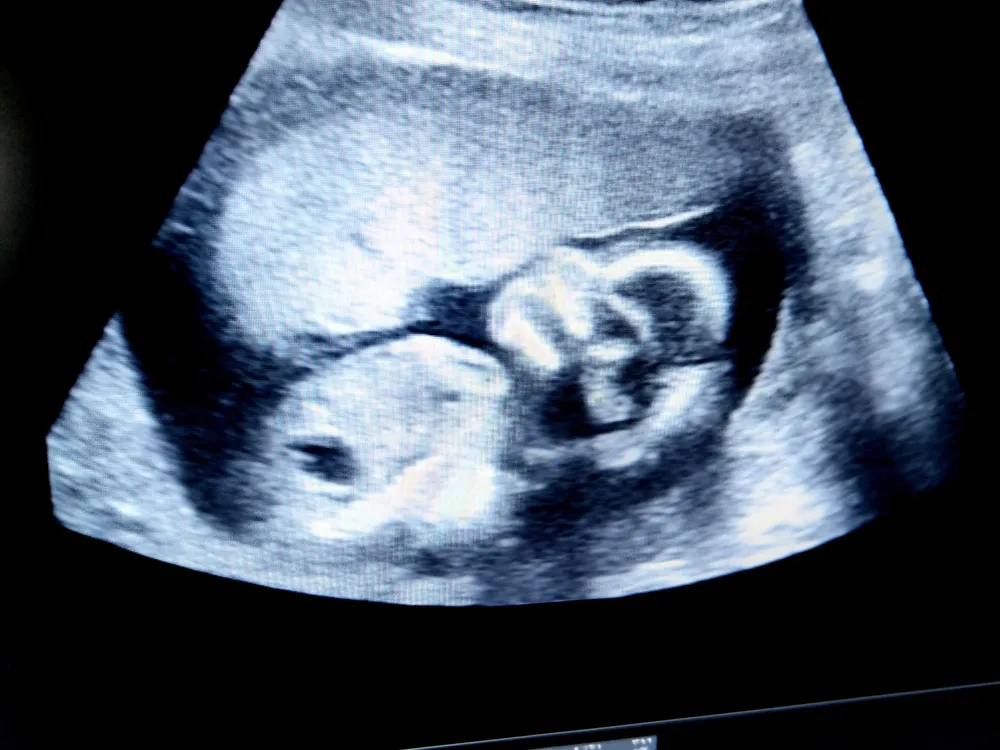

2. Hình ảnh thai nhi 24 tuần trong bụng mẹ

Các chỉ số sinh trắc của thai nhi 24 tuần cụ thể như sau:

- Đường kính lưỡng đỉnh (BPD): 53-66 mm

- Chu vi vòng đầu (HC): 204-239 mm

- Chu vi vòng bụng (AC): 176-217 mm

- Chiều dài xương đùi (FL): 39-47 mm.